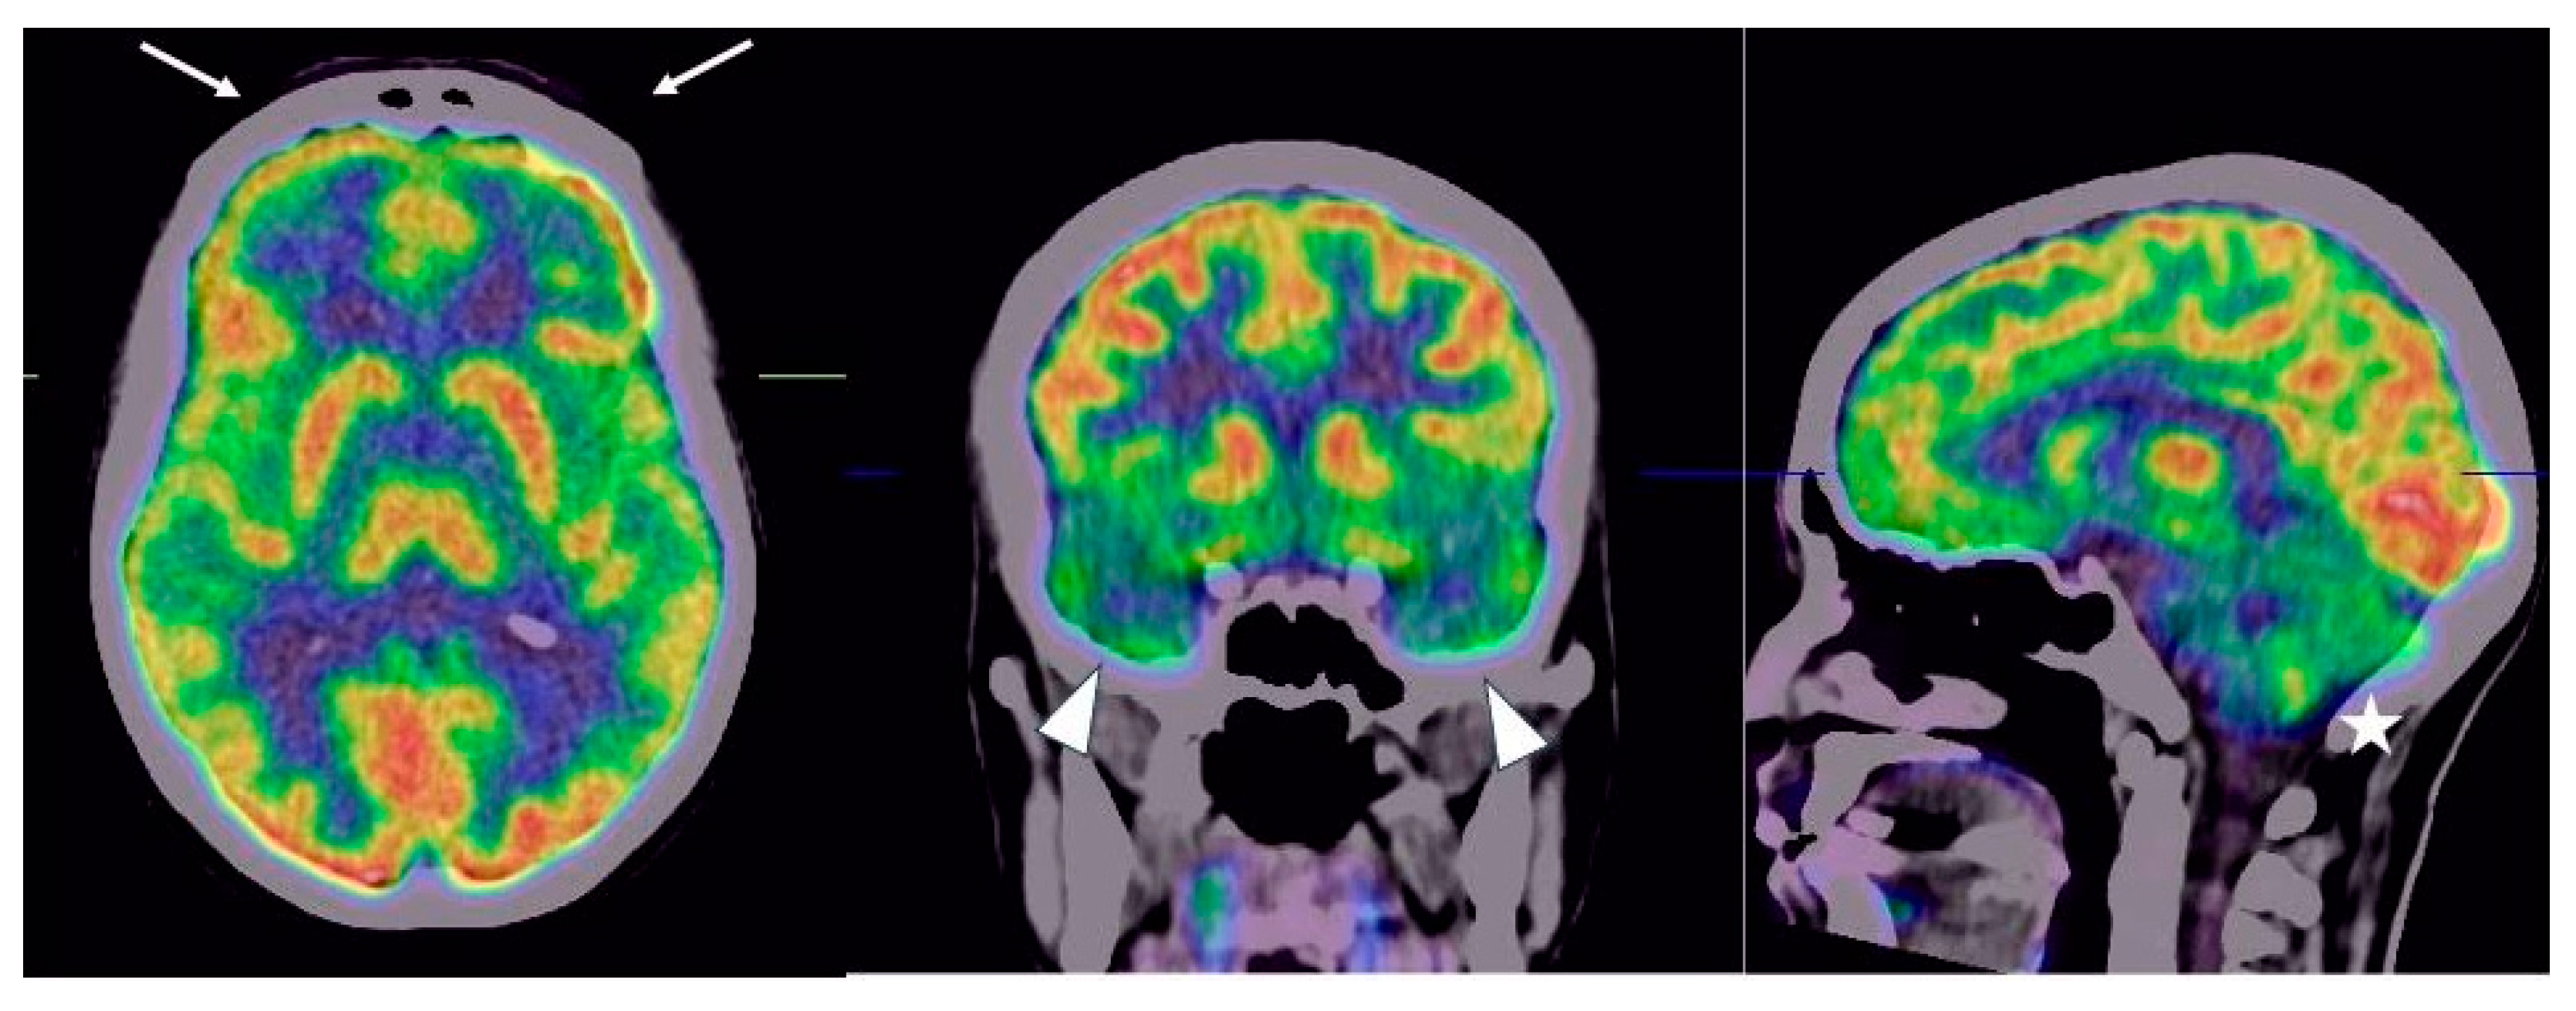

- Guedj, E.; Campion, J.Y.; Dudouet, P.; Kaphan, E.; Bregeon, F.; Tissot-Dupont, H.; Guis, S.; Barthelemy, F.; Habert, P.; Ceccaldi, M.; et al. 18F-FDG brain PET hypometabolism in patients with long COVID. Eur. J. Nucl. Med. 2021, 48, 2823–2833. [Google Scholar] [CrossRef]

- Morand, A.; Campion, J.-Y.; Lepine, A.; Bosdure, E.; Luciani, L.; Cammilleri, S.; Chabrol, B.; Guedj, E. Similar patterns of [18F]-FDG brain PET hypometabolism in paediatric and adult patients with long COVID: A paediatric case series. Eur. J. Nucl. Med. 2021, 49, 913–920. [Google Scholar] [CrossRef]

- Toniolo, S.; Di Lorenzo, F.; Scarioni, M.; Frederiksen, K.S.; Nobili, F. Is the Frontal Lobe the Primary Target of SARS-CoV-2? J. Alzheimer’s Dis. 2021, 81, 75–81. [Google Scholar] [CrossRef]

- Dressing, A.; Bormann, T.; Blazhenets, G.; Schroeter, N.; Walter, L.I.; Thurow, J.; August, D.; Hilger, H.; Stete, K.; Gerstacker, K.; et al. Neuropsychologic Profiles and Cerebral Glucose Metabolism in Neurocognitive Long COVID Syndrome. J. Nucl. Med. 2021, 63, 1058–1063. [Google Scholar] [CrossRef]

- Blazhenets, G.; Schroeter, N.; Bormann, T.; Thurow, J.; Wagner, D.; Frings, L.; Weiller, C.; Meyer, P.T.; Dressing, A.; A Hosp, J. Slow but evident recovery from neocortical dysfunction and cognitive impairment in a series of chronic COVID-19 patients. J. Nucl. Med. 2021, 62, 910–915. [Google Scholar] [CrossRef]

- Ferrucci, R.; Cuffaro, L.; Capozza, A.; Rosci, C.; Maiorana, N.; Groppo, E.; Reitano, M.R.; Poletti, B.; Ticozzi, N.; Tagliabue, L.; et al. Brain positron emission tomography (PET) and cognitive abnormalities one year after COVID-19. J. Neurol. 2023, 270, 1823–1834. [Google Scholar] [CrossRef]